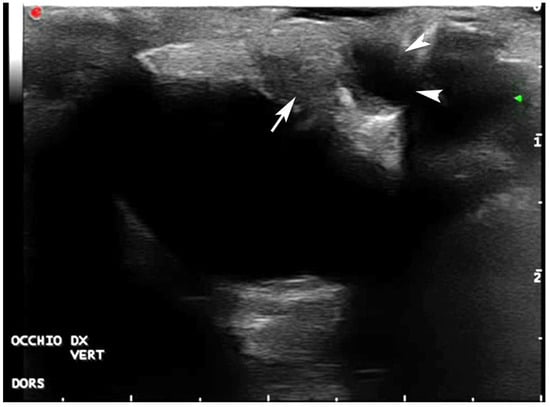

2.5. Diagnostic Imaging

- Mennonna, G.; Lamagna, B.; Affuso, A.; Greco, A.; Micieli, F.; Costanza, D.; Hochscheid, S.; Meomartino, L. Normal ultrasonographic features of loggerhead (Caretta caretta) eyes. Nat. Croat. 2020, 29 (Suppl. S1), 3–10. [Google Scholar]